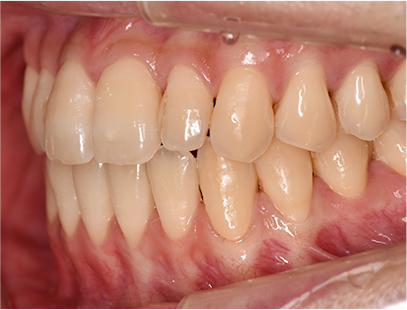

症例01|中学生の男子

前歯部の反対咬合

前歯部の反対咬合と上顎前歯のデコボコを主訴として来院されました。精査、診断の結果「前歯部に叢生を伴う反対咬合」と診断されました。

治療計画

非抜歯にて前歯の再配列、反対咬合の改善を行う事にしました。

治療前の写真と比べると前歯部の反対咬合は改善されて、上顎の前歯部のデコボコも綺麗に並べる事ができました。

また口元は上の歯が前に出たために口唇がへこんでいたことも改善されて男らしい綺麗な口元に改善できました。 治療期間は2年と6か月を必要としました。